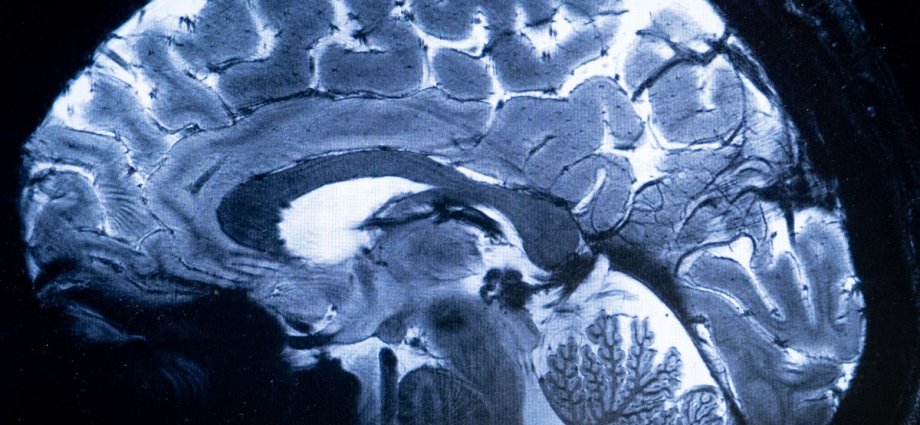

A deficiency of the metal lithium in the body could be a key factor contributing to the development of dementia in Alzherimer’s patients, a groundbreaking new study reveals.

The decade-long research, published in the journal Nature, shows for the first time that lithium occurs naturally in the brain and maintains the normal function of all its major cell types, preventing nerves from degradation.

Scientists from Harvard Medical School found that lithium loss in the human brain is one of the earliest changes leading to Alzheimer’s, while in mice, a similar lithium depletion accelerated memory decline.

In the study, scientists used an advanced type of mass spectroscopy chemical analysis method to measure trace levels of about 30 different metals in the brain and blood samples from a range of people, including cognitively healthy people, those in an early stage of dementia, and those with advanced Alzheimer’s.

Decades of studies have shown that Alzheimer’s disease involves an array of brain abnormalities, including clumps of the protein amyloid beta, tangles of the protein tau, and a loss of the brain’s protective protein REST.